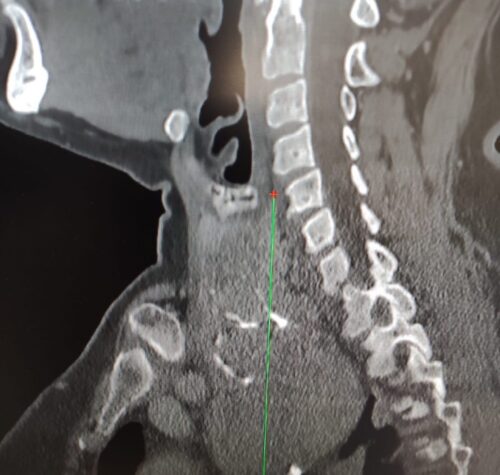

È fuori pericolo un bambino di 9 mesi arrivato in condizioni critiche all’ospedale pediatrico Giovanni XXIII di Bari per una grave insufficienza respiratoria legata a un sospetto caso di botulismo….